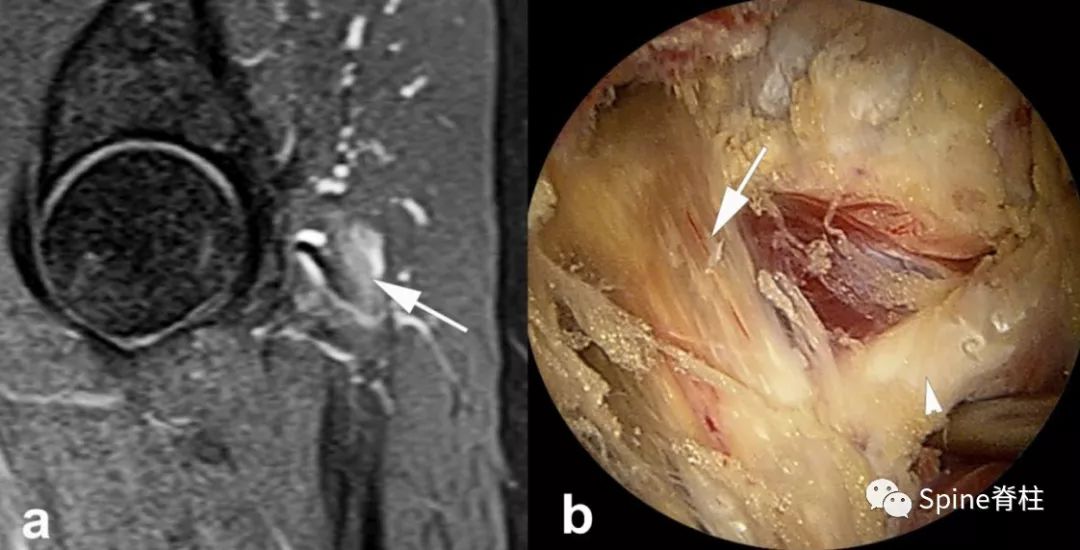

梨状肌综合征的影响学检查,主要依靠 臀部MRI ,但需排除臀部转移性恶性肿瘤、臀部结核等刺激坐骨神经。另外,随着内镜技术的发展,梨状肌综合征也可在 内镜下 诊断和治疗。